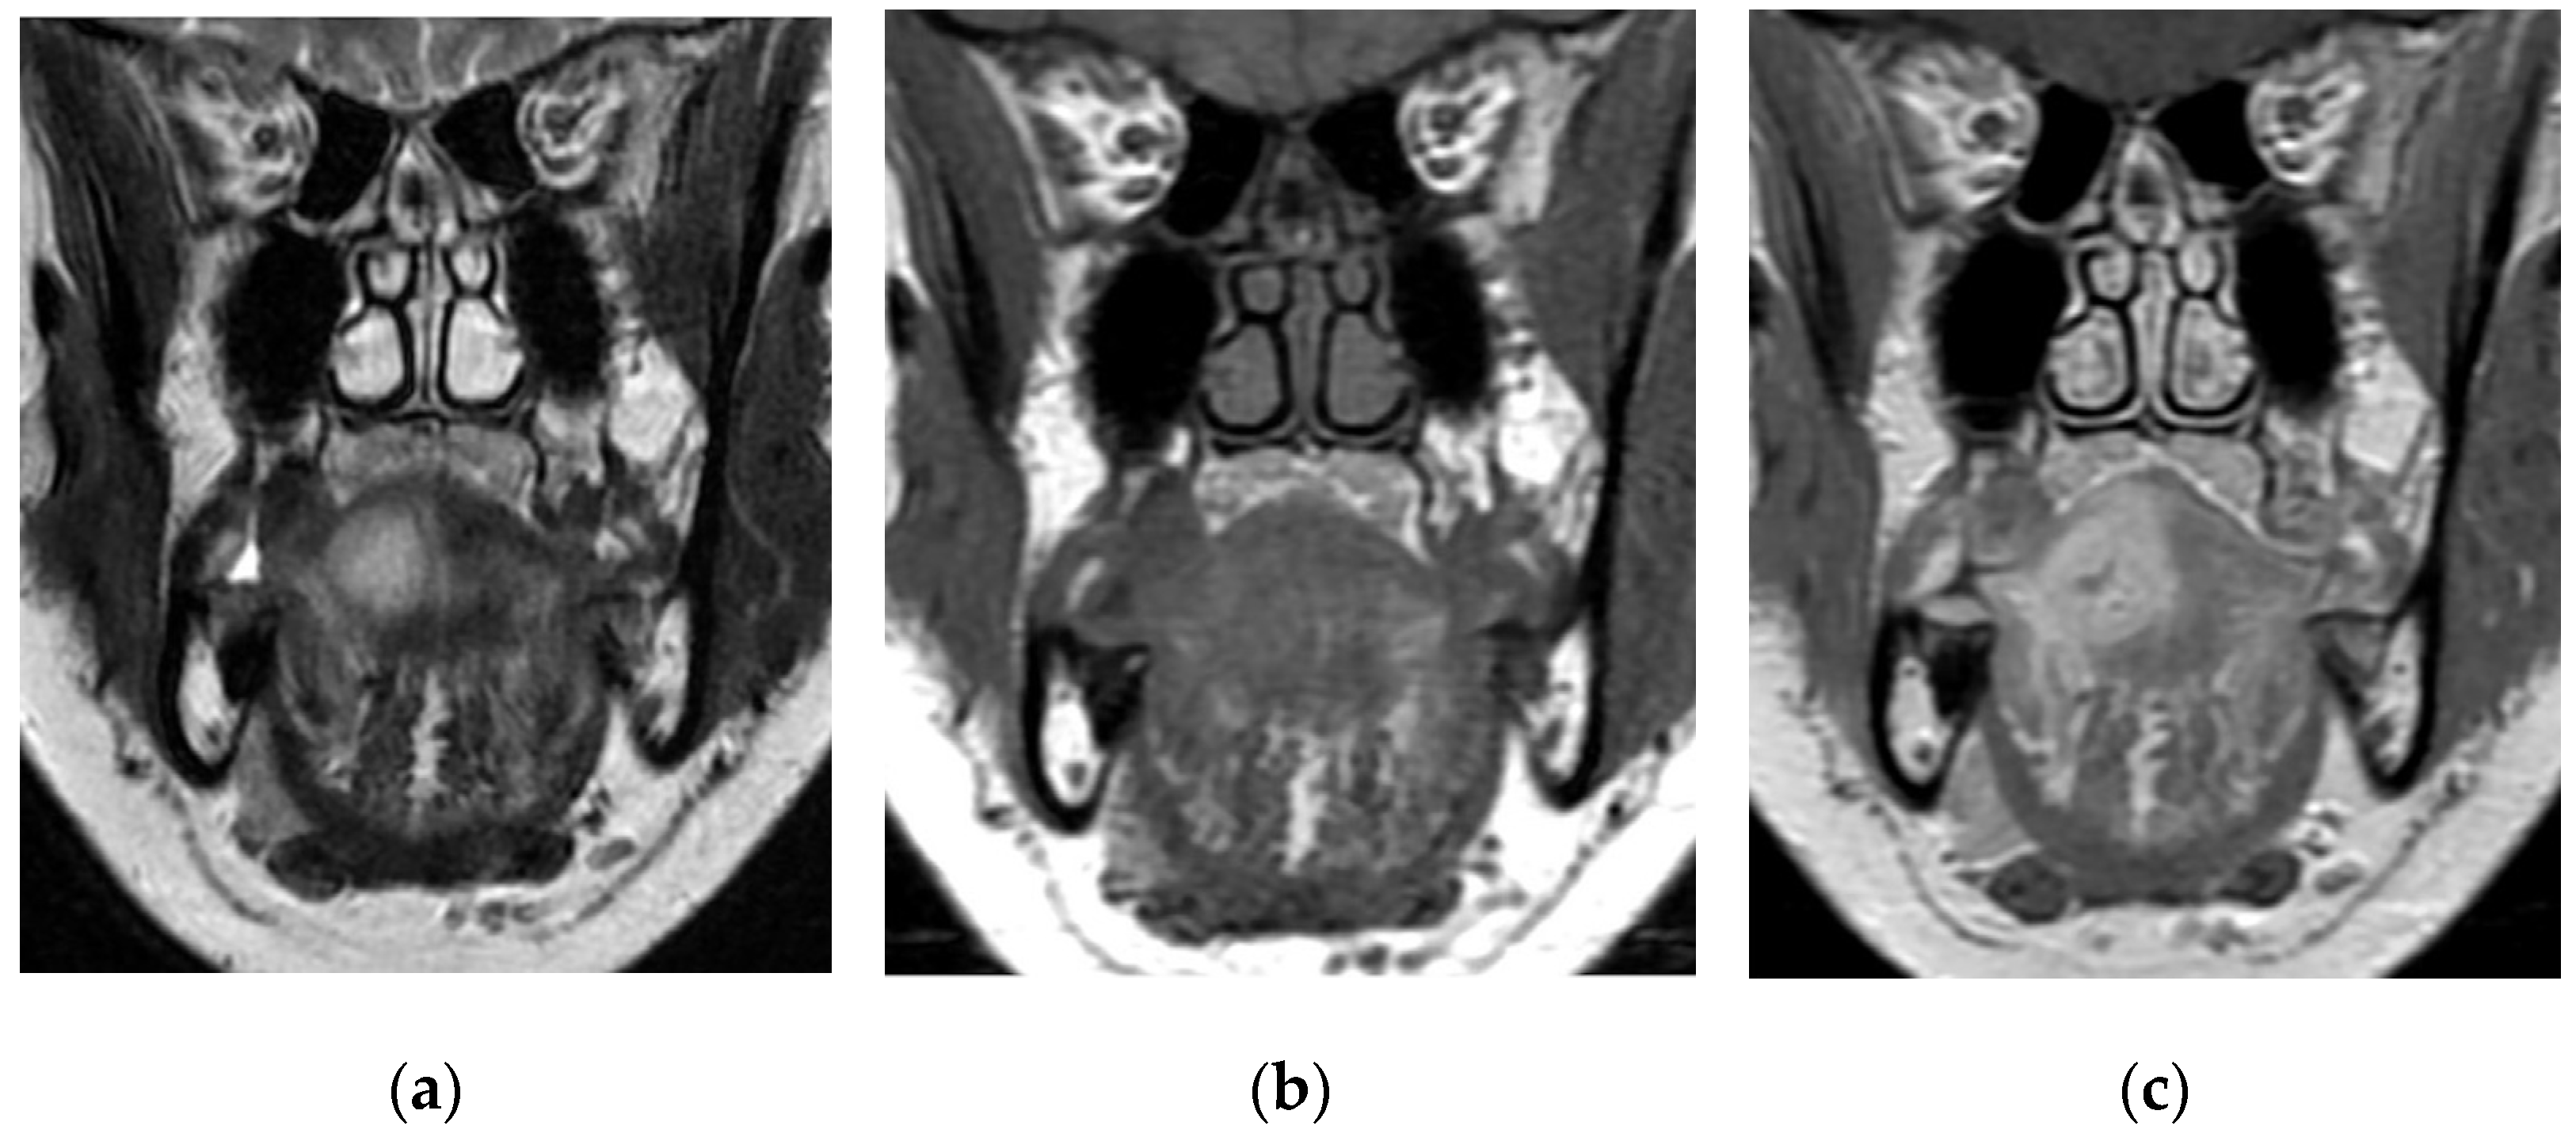

3.4. Radiological Findings

| Ozturk [6] | 7 | 1. T, O; 2. T, O; 3. O; 4. O, Dys; 5. O; 6. Dys; 7. O | 1; 2; 3; 4; 5; 6; 7 To mass | 1; 2 Leukocytosis; anaerobic bacteria; 3. Normal range, S. Viridans; 4; 5; 6; 7 Normal range | 1; 2; 3; 4; 5; 6; 7 CE MRI | 1. alcohol abuse | 1; 2; 3 Poor oral Hy | 3;4;5;6;7 Normal range | 1; 2; 3; 4: Surgery(GA) 5; 6; 7: FNA |